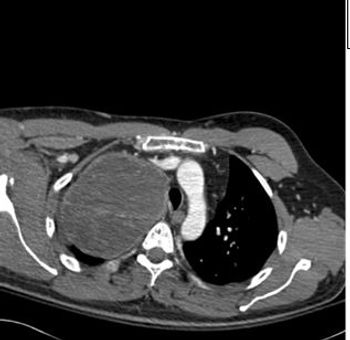

Two weeks after injury to the right chest wall and shoulder, the patient continues to have pain. He also reports numbness and tingling in his hands bilaterally. What do the ED images reveal?